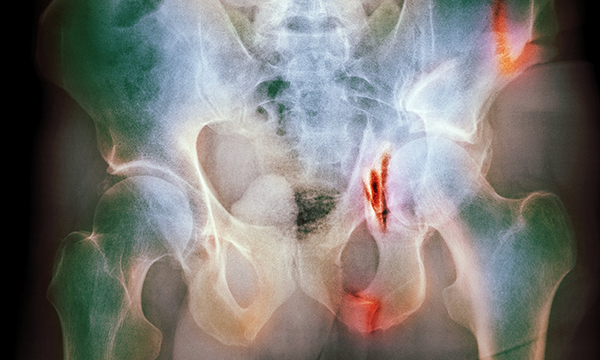

Pelvic fractures caused by high-energy trauma such as falling from a height or road traffic collisions have a high mortality rate and patients are also at high risk of life-changing injuries. High-energy trauma to the pelvis is associated with major haemorrhage and injuries to the internal pelvic organs. Emergency nurses have a fundamental role in the initial assessment and management of patients, as well as in their ongoing care once the fracture has been stabilised and bleeding is controlled. This article describes the anatomy of the pelvis, discusses the initial assessment and management of patients who have sustained high-energy pelvic trauma, details the complications of pelvic fractures and explains patients’ ongoing care in the emergency department.